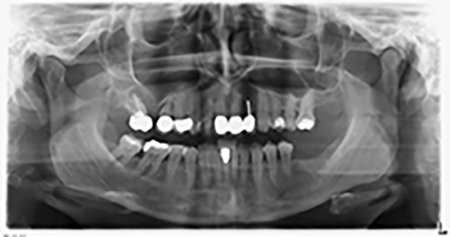

The 59-year-old patient presented with an advanced case of periodontitis, describing an unpleasant feeling and poor taste from the first quadrant in a distal direction. The clinical examination revealed generally enlarged periodontal pockets and very advanced bone atrophy in regions 16 and 14. The radiology confirmed the findings (Fig. 1). Teeth 16 and 14 could not be retained.

Image 1: Orthopantomogram with bone atrophy in region 16–14. *

About six months after teeth 16 and 14 were extracted, a digital volume tomography (DVT, Planmeca) examination was performed for planning and risk minimization purposes. It clearly showed that the bone had not regenerated to the desired volume (Fig. 2 to 7).